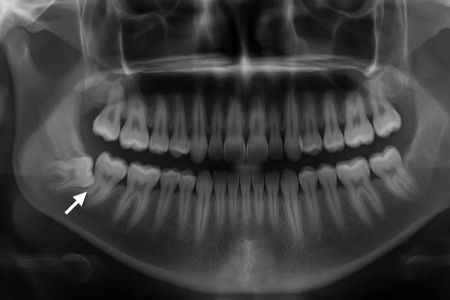

Impaktirani umnjaci

Umnjaci („osmice“) su poslednji zubi koji izrastaju i to izmedju 18-te i 26-te godine. Iz tog razloga, nekada se dešava da za njih nema dovoljno...